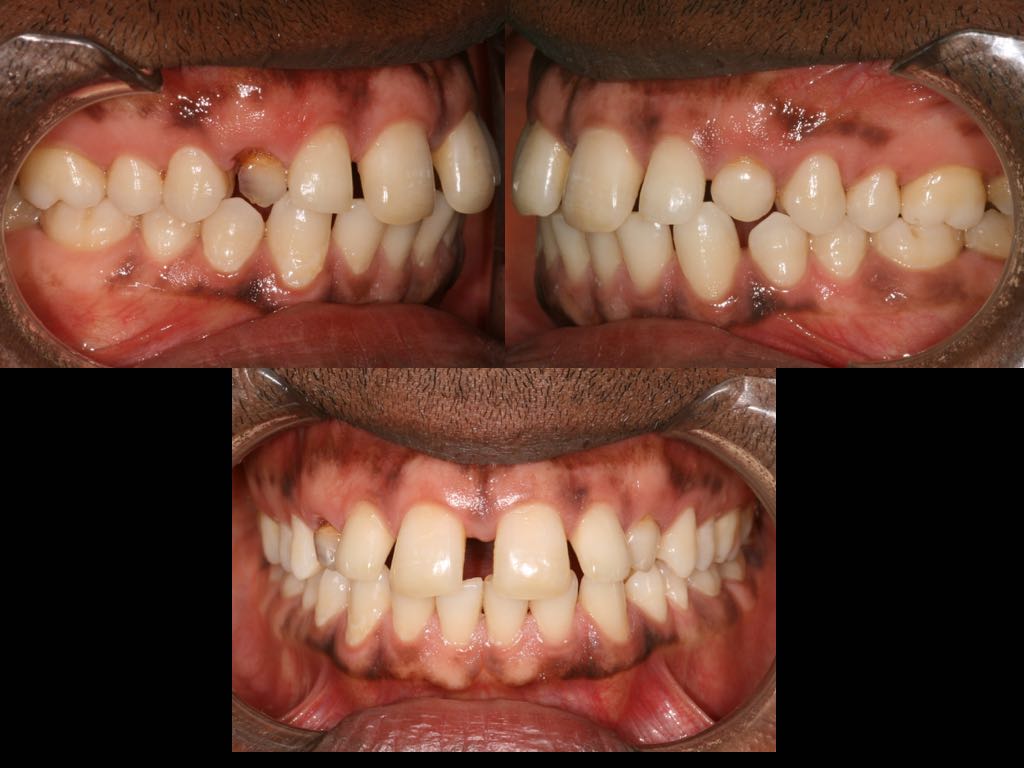

Foto e documentazione